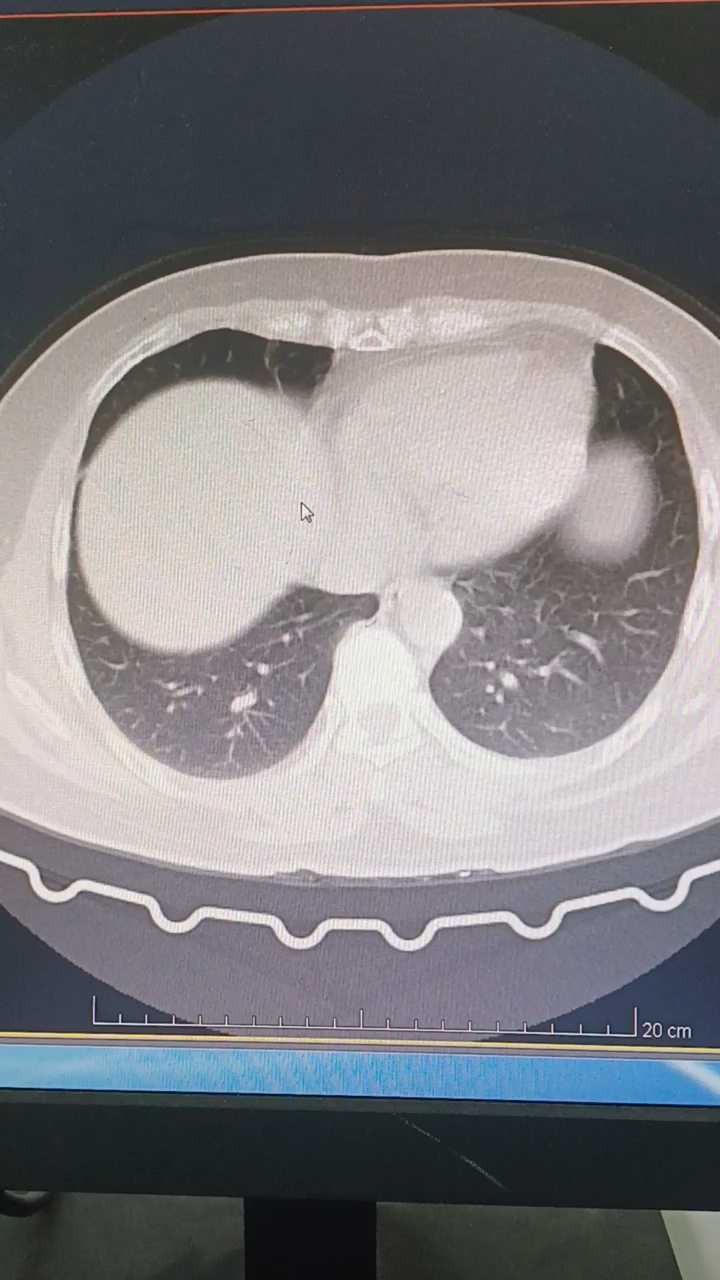

中年女性,反复咳嗽咳痰伴气促2月余,无发热畏寒等不适。既往有高血压病史。

胸膜下多发结节,周围晕征,支气管半入征,影像考虑隐球菌吗?求教各位老师,纤支镜灌洗液提示肺链,流感嗜血杆菌与影像相符吗?@唐绍宏 @李小平主任 @秒天秒地秒空气 @涂涂呼吸 @李梦杰huxi